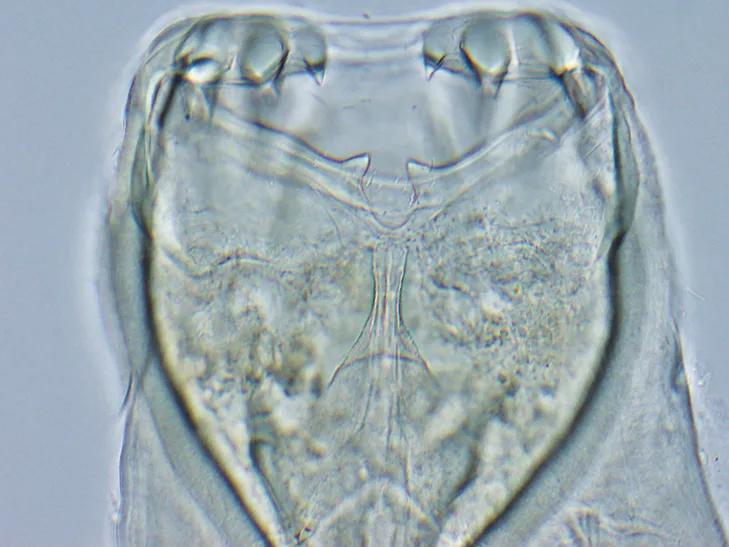

Hookworms (Figure 1) have a direct life cycle, with adult females releasing a large number of eggs (up to 10,000/day). Once passed in the feces, development of eggs to third-stage infective larvae (L3) typically takes ≈5 days, although this will vary depending on temperature. Dogs may be infected via both the oral and percutaneous routes. L3 larvae are ingested either directly or by ingestion of paratenic hosts carrying L3 tissue larvae. After penetrating the skin, L3 larvae migrate via the bloodstream to the lungs, penetrate the alveoli, migrate up the bronchial tree to the trachea, are expectorated via coughing, are swallowed, and enter the small intestine, where they complete development into the adult stage. The prepatent period for either route of infection is 15 to 26 days. Following skin penetration in dogs older than 3 months of age, A caninum L3 larvae often undergo somatic migration to the muscle, fat, and other organs; encyst; and enter a hypobiotic state.

Anterior end of adult A caninum. The buccal capsule (ie, mouth) contains the characteristic 3 pairs of teeth.